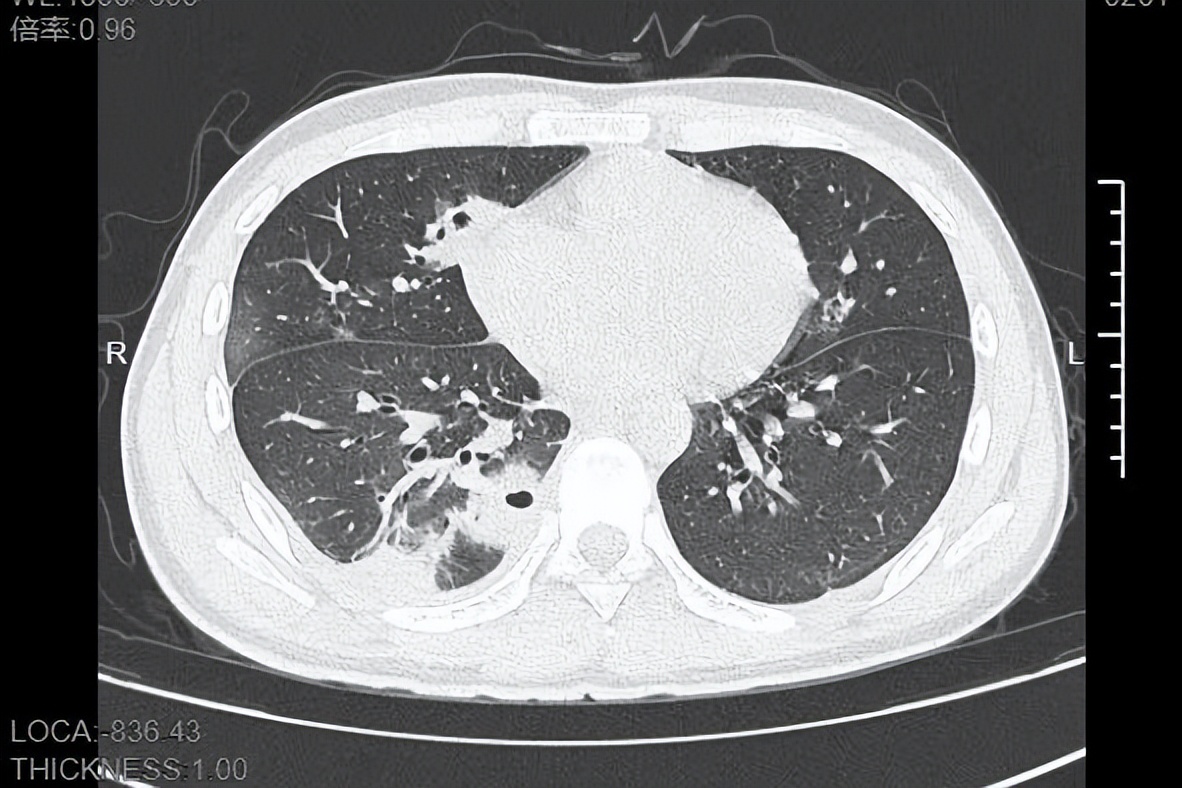

熬到第三天,小林已经烧到39℃,赶紧来到宁波大学附属第一医院就诊。接诊的呼吸与危重症医学科丁群力主任医师一看他的症状,立刻安排了CT检查。结果显示:小林的肺里有十几个空洞,部分肺组织已经坏死,这是典型的血源性肺脓肿。

像小林这样,当细菌跑到肺组织上后,就会开始疯狂破坏肺细胞,引发局部炎症。随着炎症加重,肺组织会逐渐坏死、液化,最终形成一个个空洞。

如果没有及时就医,风险还会持续升级,轻则导致肺脓腔破裂,引发脓胸、脓气胸,胸腔里积满脓液,重则细菌会再次扩散到肝脏、心脏等关键器官,甚至引发脓毒症休克,危及生命。

即便最终治愈,严重的肺组织坏死也可能留下后遗症,比如肺功能下降,影响后续的正常呼吸。